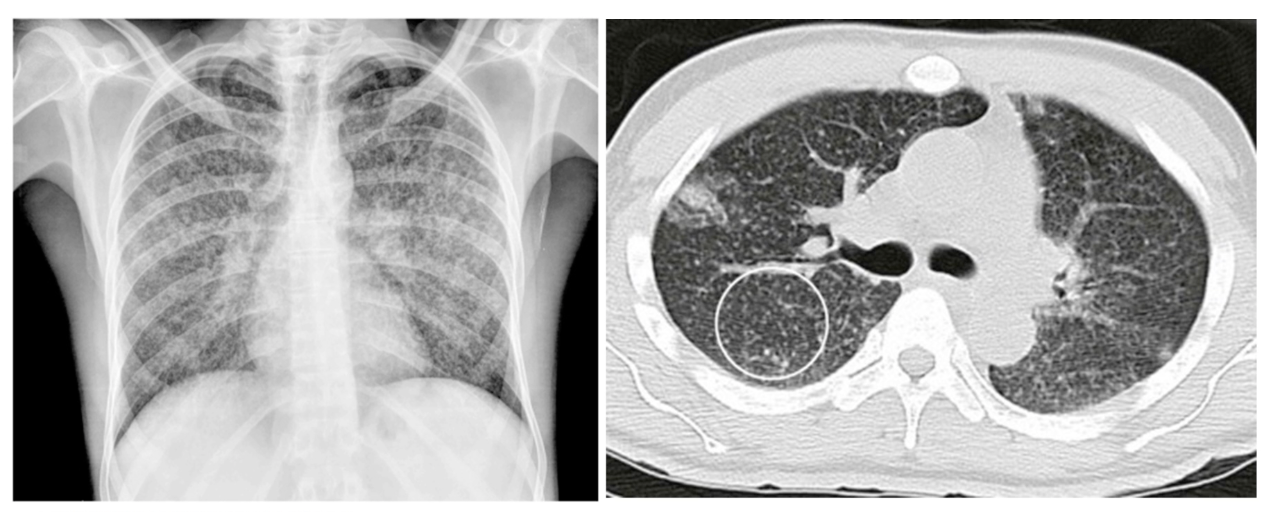

What CT findings are typical for segmental/bronchopneumonia

• Multifocal patchy consolidation of secondary lobules with no air bronchogram

• Can also have ground glass opacity and thickened bronchial opening

What are some usual causes for segmental/bronchopneumonia?

1. lobar pneumonia (generally from bacteria that cause CAP) 2. bronchopneumonia (may be seen if you catch pneumonia early enough and doesn't progress to lobar pneumonia) - image 3. interstitial infiltrates (generally from viruses that cause CAP)